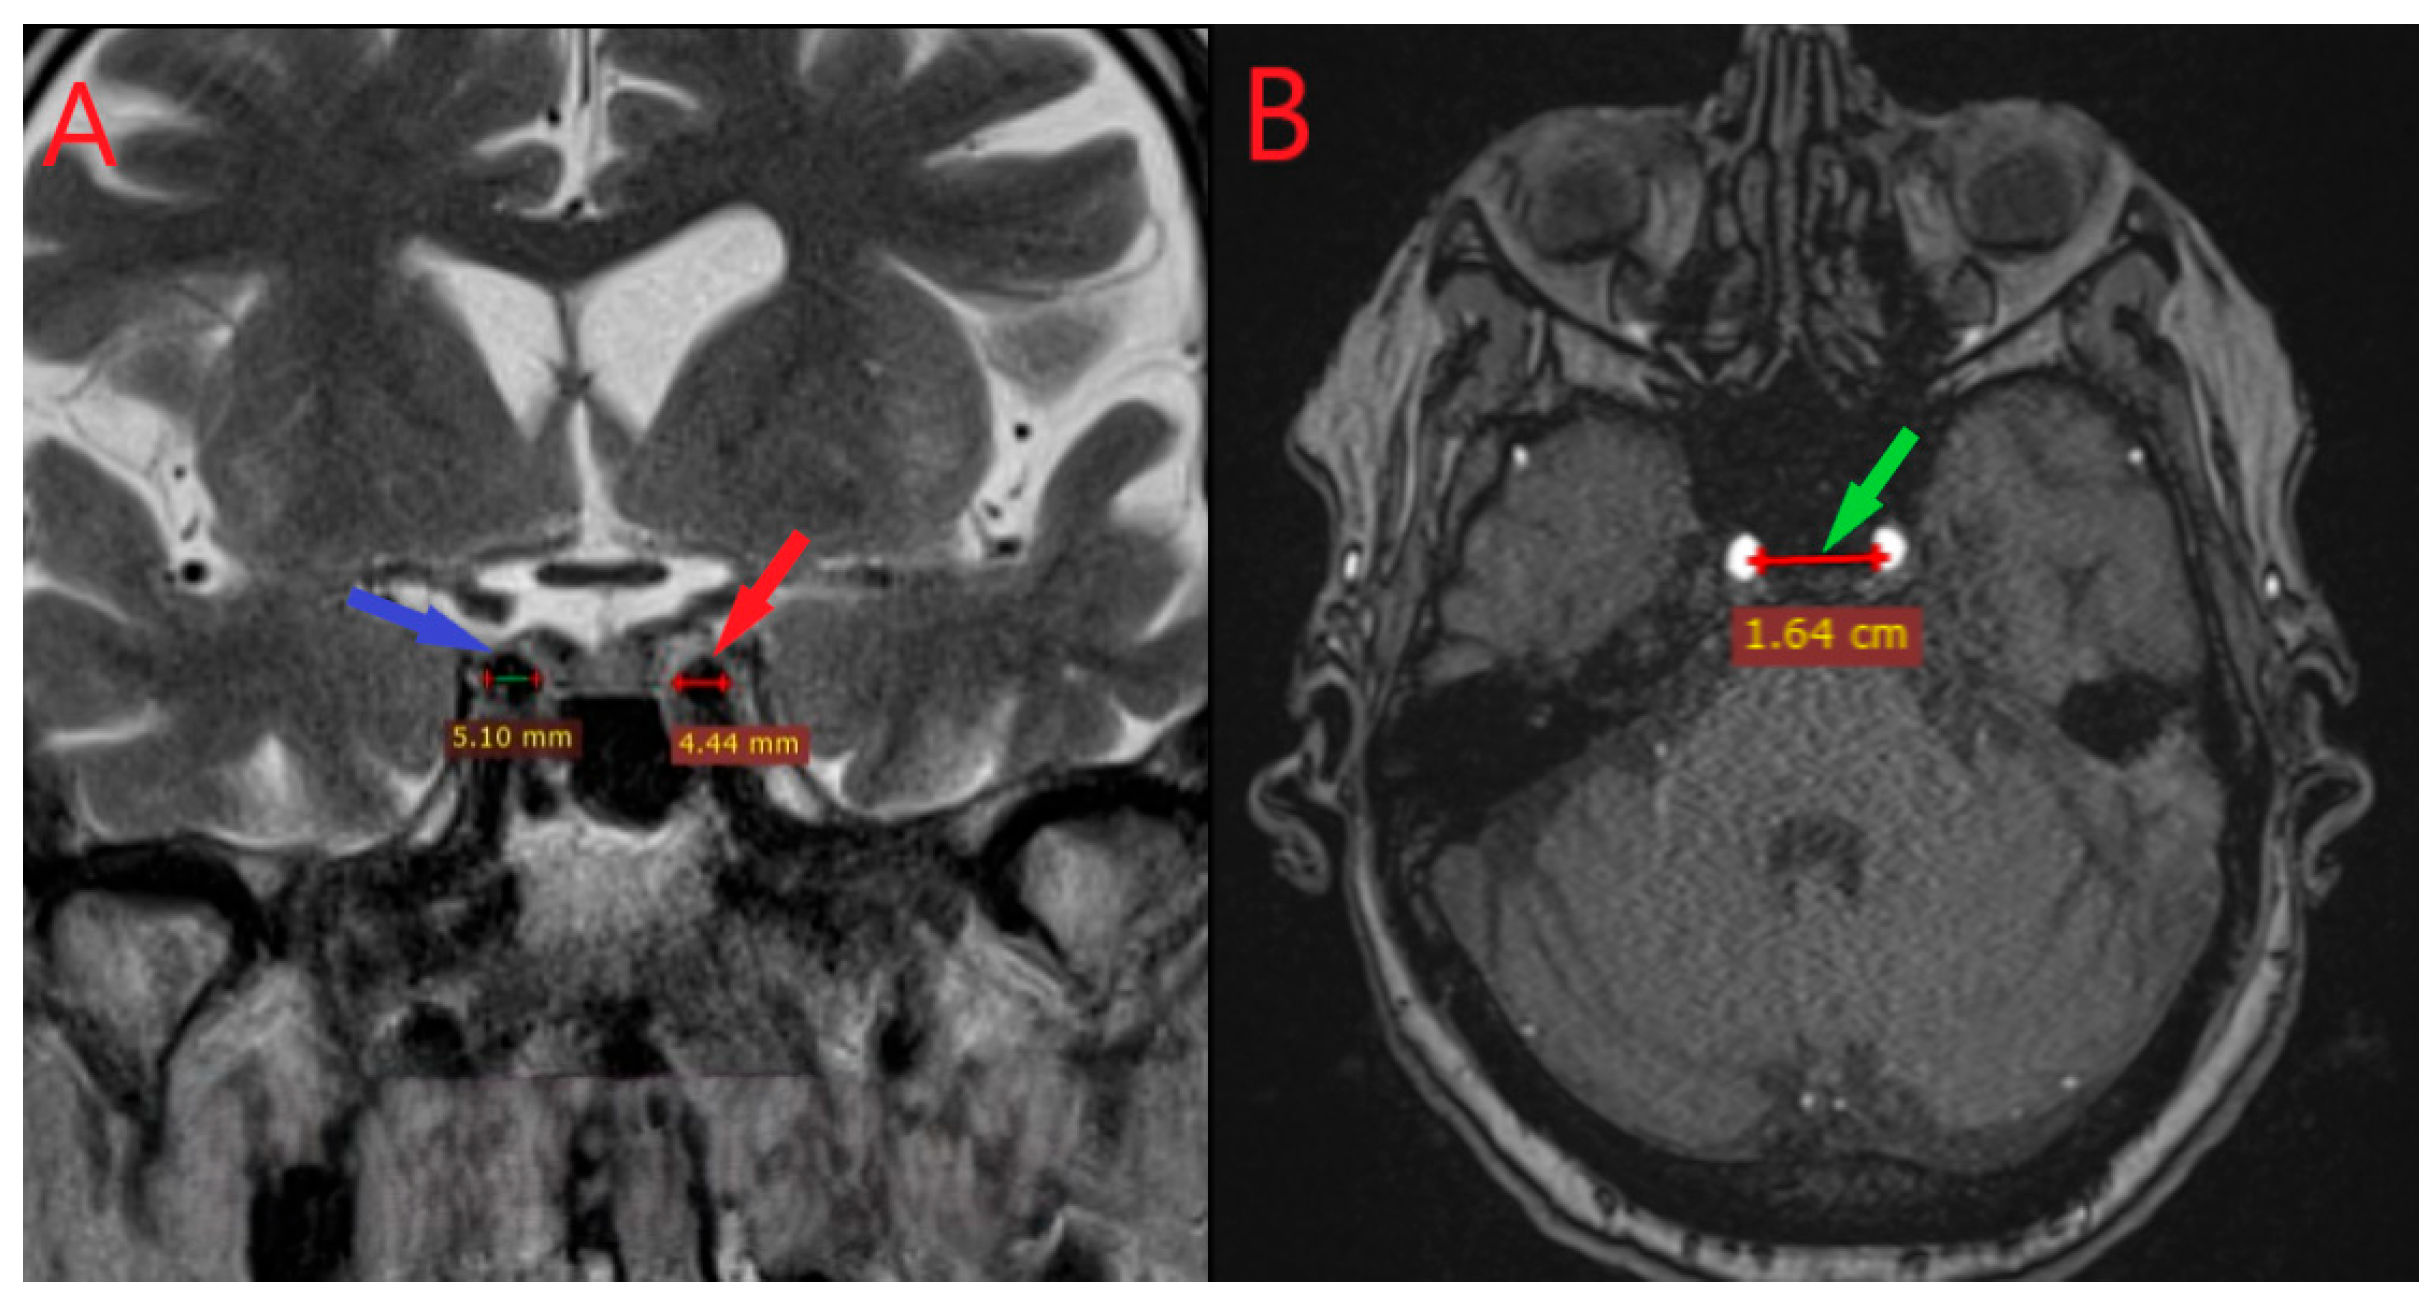

2.3. Imaging and Morphometric Measurements